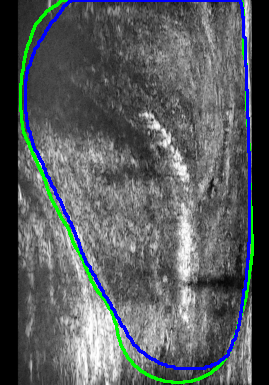

Figure 4 presents the performance evaluation of three loss functions—Adaptive Focal Loss, AG-BCE Loss, and PyTorch Focal Loss—on three test images. Each row in the figure corresponds to the segmentation results of one loss function, while the columns represent the respective test images. A legend at the top provides the color coding for the ground truth and the outputs of the three loss functions, allowing for a direct visual comparison of their performance.

The visual analysis of segmentation results, illustrated in Figure 5, demonstrates that Adaptive Focal Loss consistently achieves more accurate segmentation, particularly in regions with low contrast, high noise, or complex anatomical variations, closely aligning with the ground truth.

1.

Test Image 04: The Adaptive Focal Loss function excelled in capturing the prostate boundary, especially in the lower-left region obscured by speckle noise. By comparison, AG-BCE and PyTorch Focal Loss exhibited significant deviations, notably under-segmenting the prostate and failing to depict the boundary accurately.

-

2.

Test Image 11: The Adaptive Focal Loss function demonstrated superior performance in the upper-right region, where the prostate boundary was subtly defined against surrounding tissue. AG-BCE failed to capture finer details, producing a less smooth boundary and shifting it inward, while PyTorch Focal Loss over-segmented, extending beyond the prostate.

3.

Test Image 14: Despite complex artifacts in the lower region, Adaptive Focal Loss maintained a boundary closely resembling the ground truth. AG-BCE exhibited minor mismatches, particularly in the lower-right corner, while PyTorch Focal Loss underperformed, displaying over-segmentation and boundary deviations.